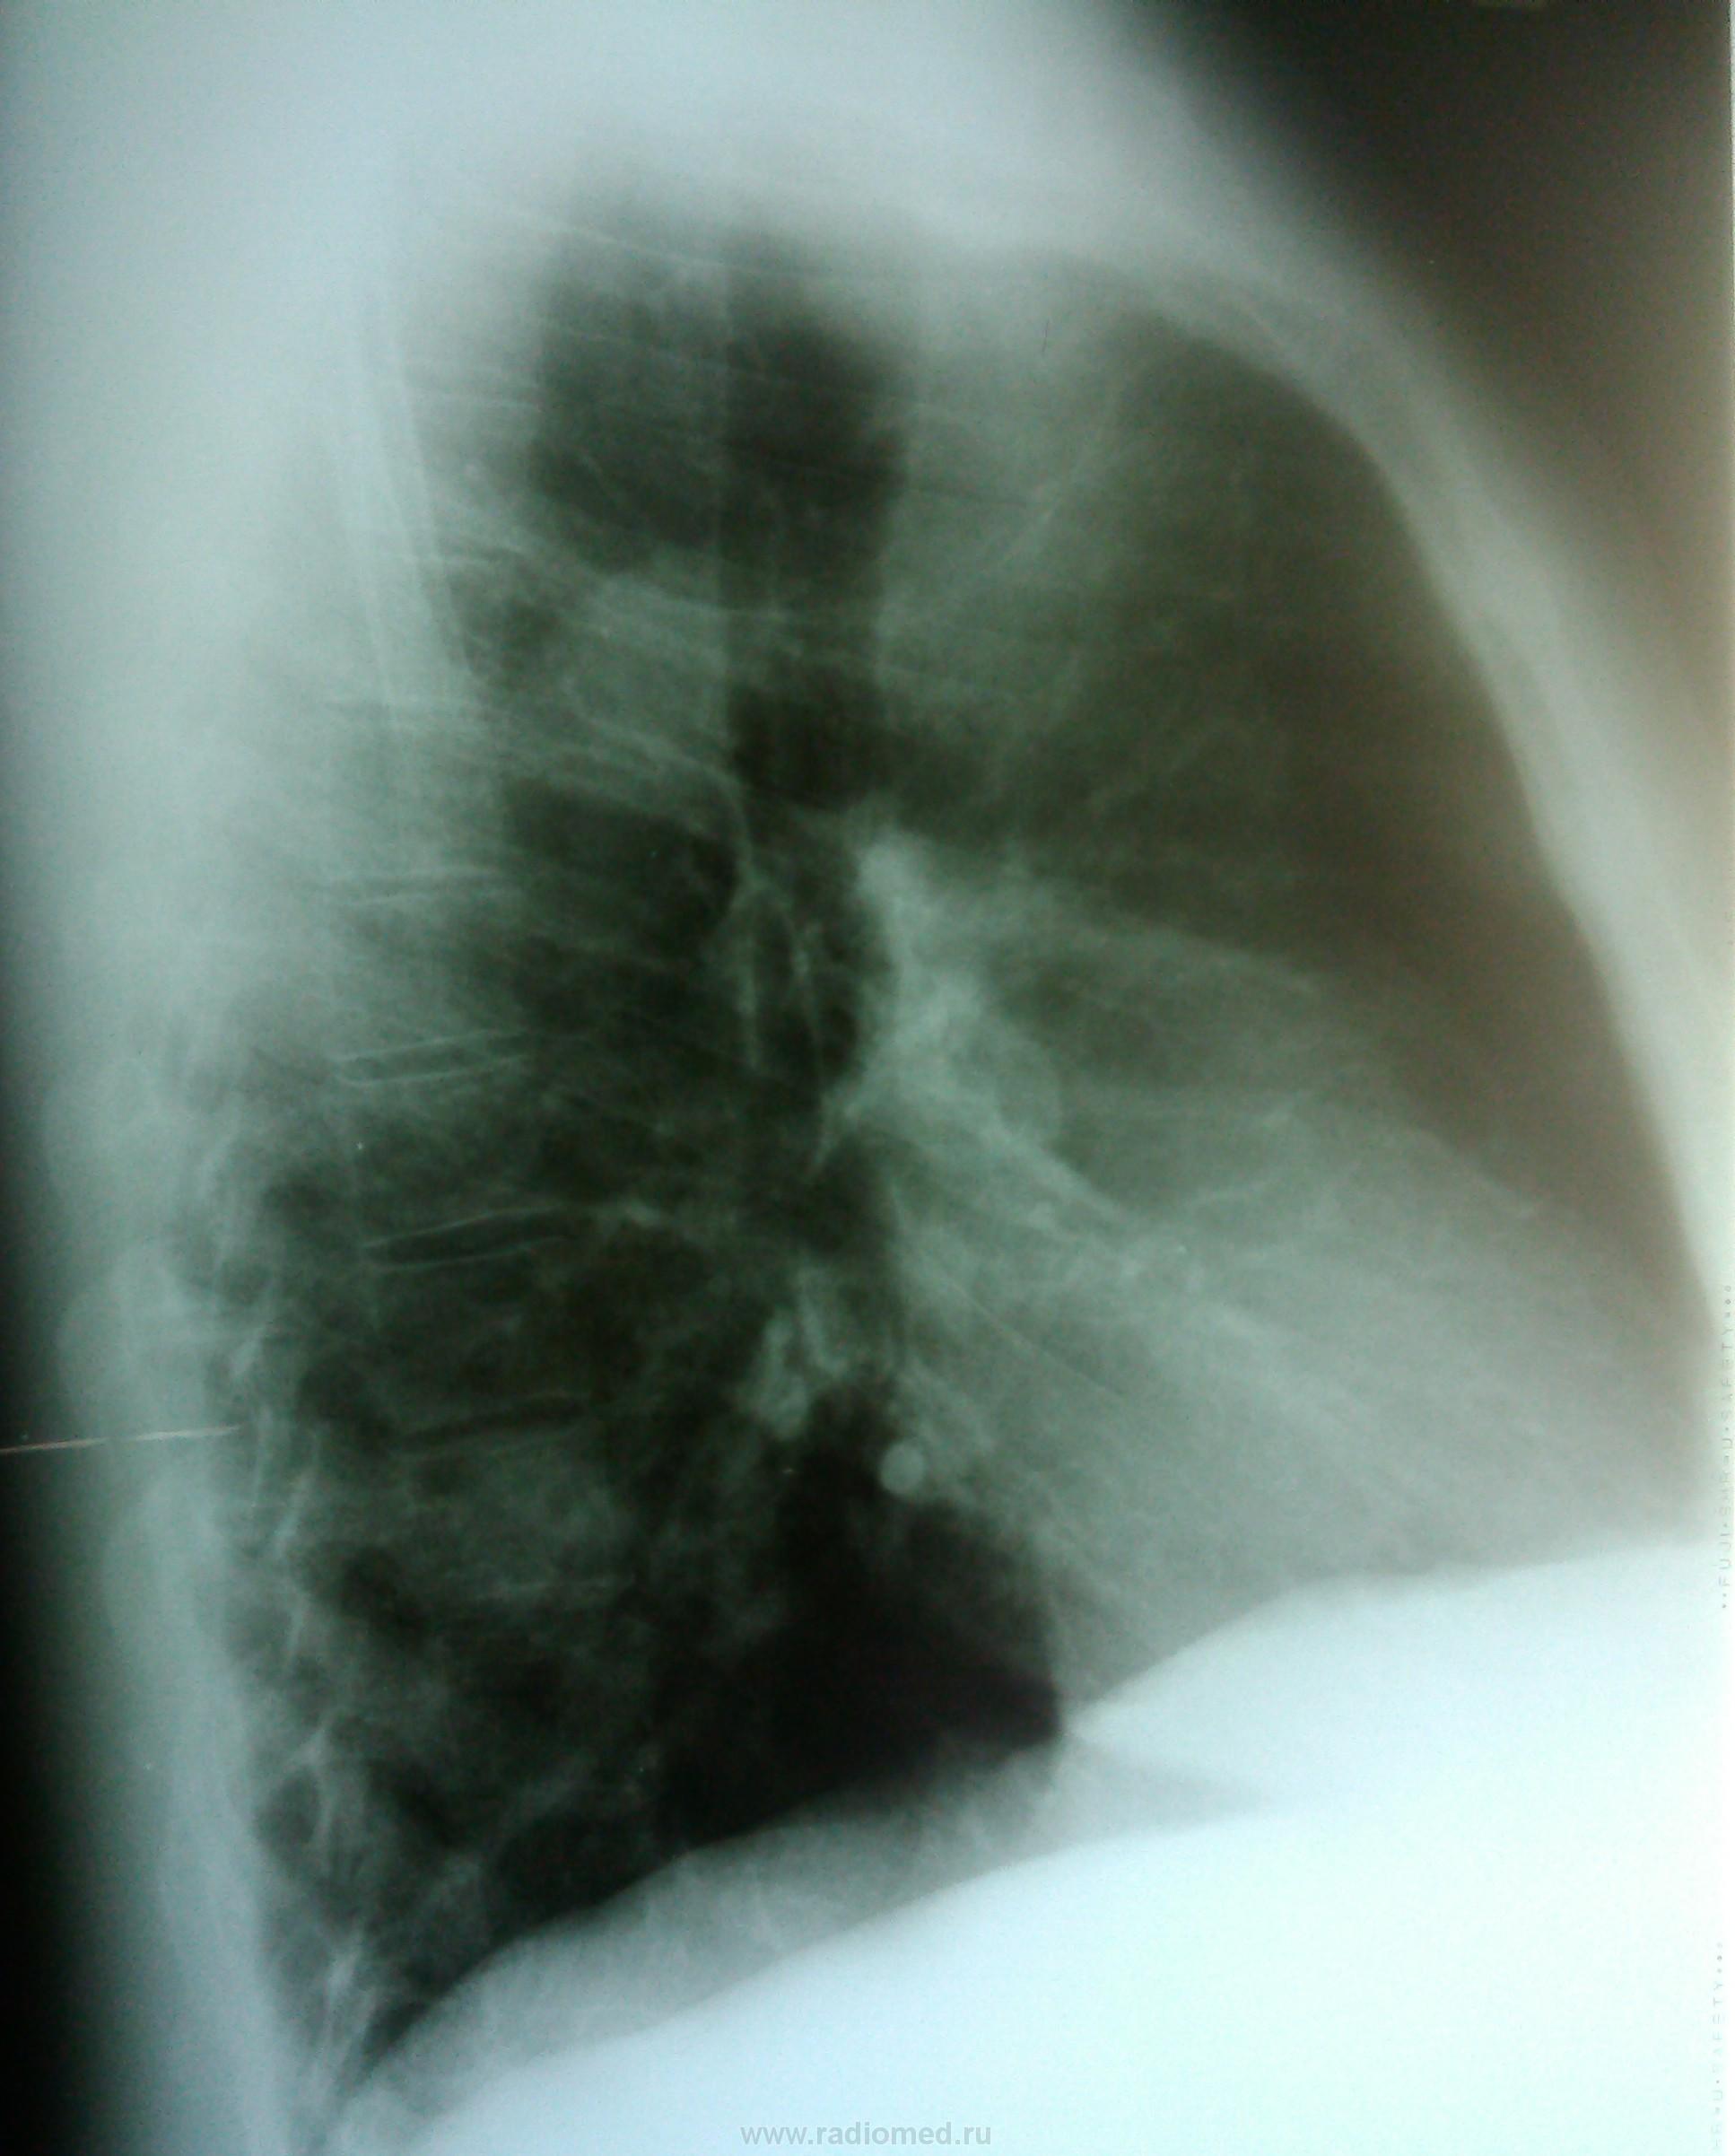

май 2014 г.

Пермферический рак нижней доли правого легкого в S9-10(учитывая отрицательную динамику за год)

Согласна с коллегами. Справа в S 10 периферическое образование, учитывая рост, более вероятно  C-r.  Cлева в среднем поле   воздушная киста

периферический рак справа + кисты в левом легком  в средних и нижних отделах